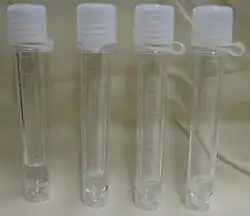

O líquor deve ser colhido em ambiente hospitalar, através de punção suboccipital (logo abaixo do crânio) ou lombar (entre a terceira, a quarta e a quinta vértebras lombares).[4] A técnica requer esterilidade absoluta e deve ser executada por um profissional médico treinado. Imediatamente após a coleta, o paciente deve submeter-se a um período de repouso relativo e hidratação forçada. Usualmente colhe-se por gotejamento em três tubos estéreis identificados e marcados numericamente. O primeiro tubo se destina às análises bioquímicas e sorológicas, o segundo tubo é destinado à microbiologia e o terceiro, à citologia. Opcionalmente, colhe-se um quarto tubo para análise microbiológica. Sendo um líquido nobre, todo esforço deve ser tomado para se evitar a necessidade de nova coleta, e o fluido colhido em excesso deve ser armazenado, após a centrifugação e efetuação das análises, sob congelação.

A análise clínica inicia-se já no processo de coleta, quando deve ser verificado se o fluido corre sob pressão (indicativo de hipertensão intracraniana) ou apenas em gotejamento lento (normal).[2] A aparência deve ser límpida e incolor (compara-se o líquor a um tubo idêntico contendo água destilada contra um fundo contrastante). Aparências anormais são descritas como cristalino ou turvo, leitoso, xantocrômico (de coloração melhor descrita como rosada, laranja ou amarela) ou sanguinolento (hemorrágico). No caso de líquor hemorrágico, deve-se diferenciar o acidente de punção (tubo inicial mais escuro que os demais, gradativamente mais claros, resultante da contaminação por sangue periférico durante a coleta) e a hemorragia intracraniana (todos os tubos de mesma coloração). A xantocromia pode ser causada pela presença de produtos de degradação dos eritrócitos, presença de bilirrubina, caroteno, proteínas em grande quantidade, ou pigmento de melanoma. Na meningite tuberculosa, pode formar-se no líquor deixado em repouso uma fina película semelhante a uma teia (retículo de Mya).